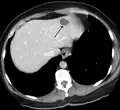

ورم وعائي دموي في الكبد كما يظهر في صورة الأشعة المقطعية.